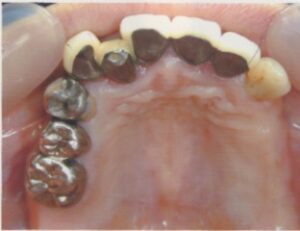

- 10年前から他の歯科医院にて部分的な治療を受けたが、見た目が良くない・噛めないとのことで再治療を希望された。アングルクラスⅠであった。左上奥歯がない。

- 上顎左側にインプラントを3本し、

- オールセラミック4本にて被せ物を行なった。

- 審美的な仕上がりで、患者自身も満足した。23年経過し良好である。

現在は2〜3ヶ月おきのメインテナンス中である。